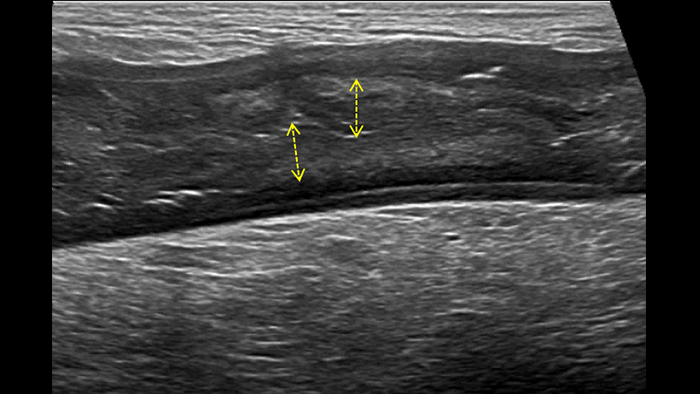

Dans cette présentation, nous exposerons en détail l’intérêt potentiel de la sonde linéaire PureWave eL18-4 pour répondre aux deux premières questions précédemment posées: le diagnostic final de la maladie inflammatoire chronique de l’intestin grâce à l’imagerie haute résolution des changements structurels dans les parois intestinales pathologiques et la recherche de signes d’une inflammation active grâce à la visualisation des microvaisseaux avec le mode d’imagerie MFI. L’imagerie 2D haute résolution est la première étape. Depuis longtemps, l’échoendoscopie nous démontre que l’échostructure des parois intestinales est formée de 5 couches échographiques corrélées aux couches histologiques. De même, une exploration échographique percutanée du tube digestif doit permettre d’identifier les couches intermédiaires entre les couches externes hyperéchogènes qui ne constituent qu’une interface entre la paroi intestinale et la graisse péri-digestive d’un côté et le lumen intestinal de l’autre côté :

Cet aspect est constant dans tout l’intestin grêle et le côlon. Si l’épaisseur pariétale est variable, elle demeure cependant toujours inférieure à 5 mm. La ligne muqueuse peut être linéaire ou ondulée en présence de villosités ou de plis. Par ailleurs, le péristaltisme peut gêner l’identification des couches. La nouvelle sonde eL18-4 offre de manière complémentaire la haute résolution et la cadence d’acquisition requises pour pouvoir visualiser nettement les couches de la paroi intestinale. A titre d’exemple, voici un comparatif de la maladie de Crohn et de la rectocolite hémorragique (même échelle) :